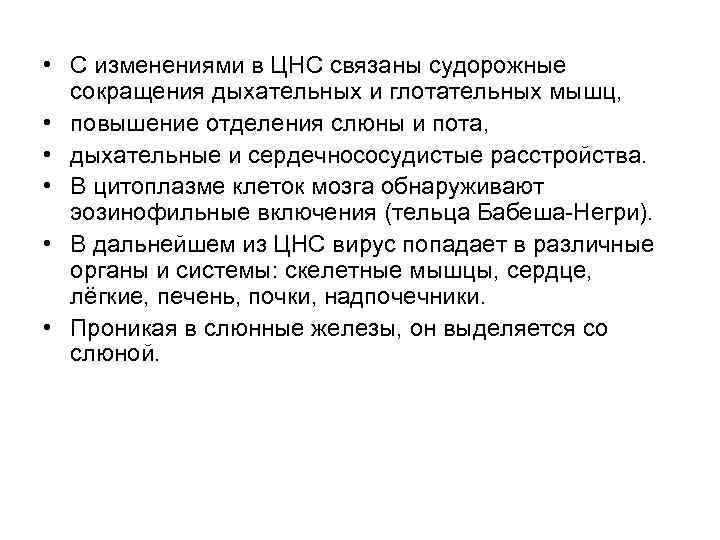

• С изменениями в ЦНС связаны судорожные сокращения дыхательных и глотательных мышц, • повышение отделения слюны и пота, • дыхательные и сердечнососудистые расстройства. • В цитоплазме клеток мозга обнаруживают эозинофильные включения (тельца Бабеша-Негри). • В дальнейшем из ЦНС вирус попадает в различные органы и системы: скелетные мышцы, сердце, лёгкие, печень, почки, надпочечники. • Проникая в слюнные железы, он выделяется со слюной.